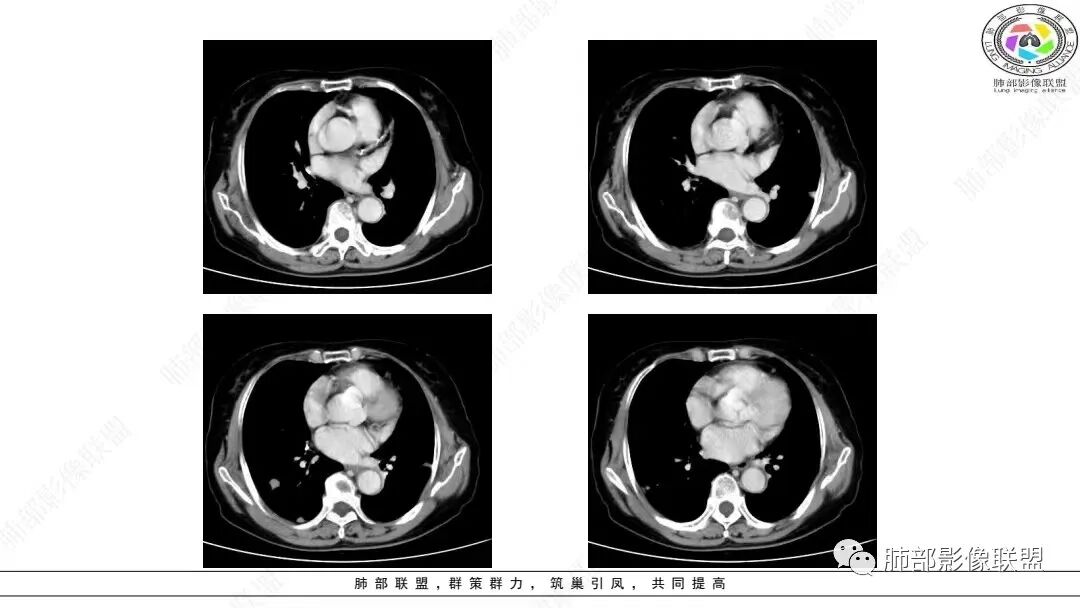

2.影像学特点:右肺上叶前段胸膜下不规则较大团块影,边界清楚欠光整,浅分叶,肺血管支气管出入,边缘膨隆胸膜凹陷具有一定张力,未见典型粗短毛刺,部分围以边界清楚的磨玻璃影,灶周小叶间隔增厚。块影密度不均,渐进性强化,可见砂砾样钙化,未见明显液化坏死或空洞。增强后病灶显示渐进性强化。MIP显示病灶内肺动脉穿行、并部分肺动脉受侵变细。纵隔及右锁骨上(胸廓入口)见肿大淋巴结。两肺可见多发大小不一的结节影,边界清楚,随机分布。

胸椎体溶骨性吸收破坏,突破骨皮质。腹部扫描未见肿块影。

3.总结:老年女性。无明显呼吸系统临床症状。实验室检查未见明显异常。右肺上叶前段团块➕右侧颈部、纵隔淋巴结肿大➕两肺多发结节。符合恶性病变。

病灶较大较光整,支气管出入,缀以边界清楚磨玻璃影,有一定张力,不均匀强化,疑及肺腺癌或者大细胞肺癌都在情理之中。双肺多发病灶,符合转移瘤特征。     注意胸椎体溶骨性吸收破坏,突破骨皮质,经验上这样的改变更支持转移而不支持淋巴类肿瘤。